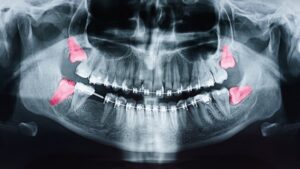

Wisdom teeth are the final set of molars that typically develop in the late teenage years or early adulthood. Because they are so common, many people assume that everyone has wisdom teeth. However, this isn’t always the case. Some people have fewer wisdom teeth than expected, and others may not develop them at all.